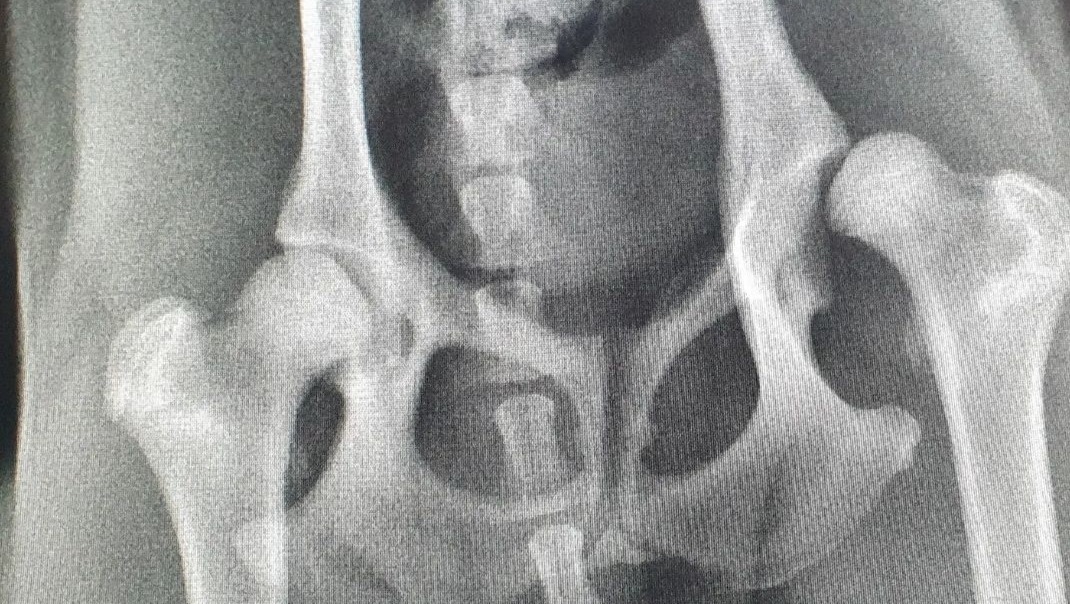

Ella's left hip dislocates out of its socket extremely on the preliminary x-rays and we were sent for follow up x-rays a month later after intensive bedrest (and a month for a puppy is a long time!)

These follow-up x-rays confirmed that speciality orthopaedic surgery needed to be completed with a cost of $7,500 per hip if Ella did not respond well to rest and pain management.